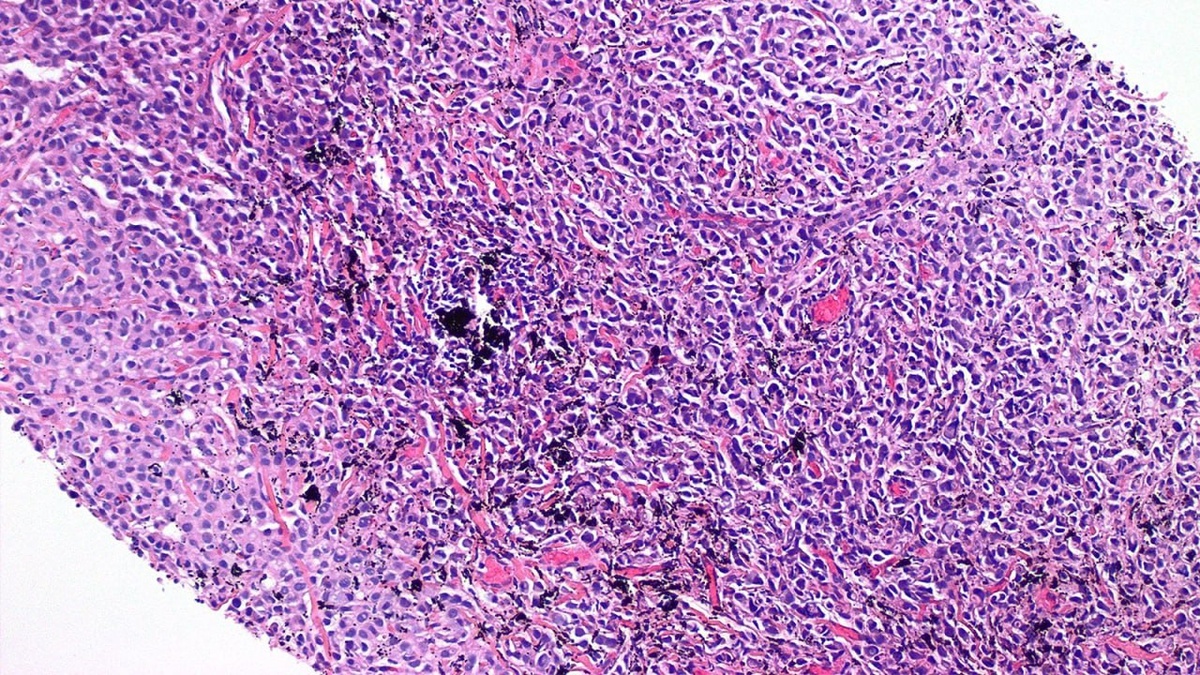

Случай метастатического рака молочной железы vs пигмент от татуировки 🔬

Не прекращайте поиски после первого найденного признака!

В представленном препарате биопсии обращают на себя внимание чернила от нанесенной на руку пациентки татуировки. Однако при детальном исследовании в препарате также обнаруживается метастатический дольковый рак, который маскируется под более заметным пигментом.